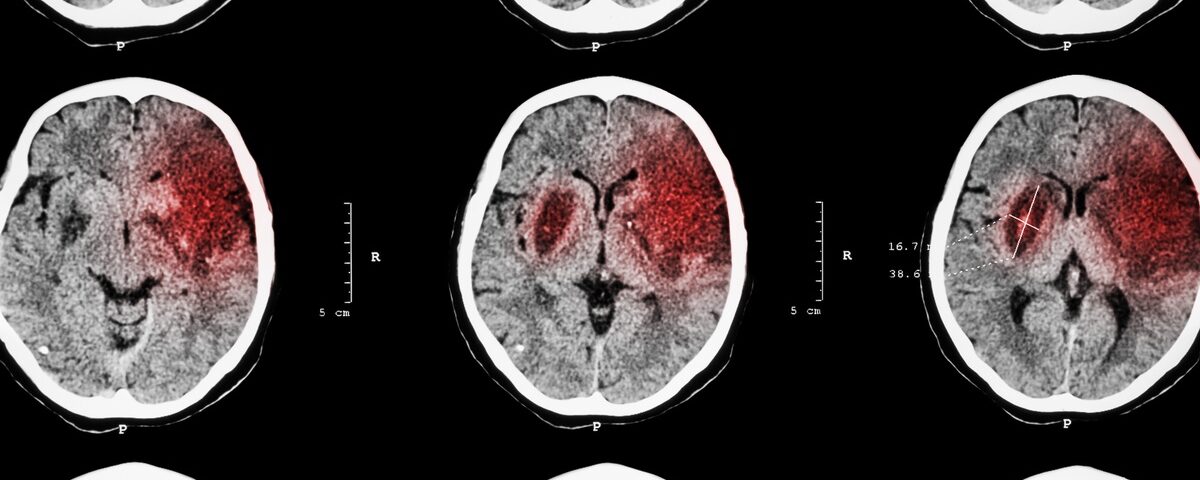

tPA is most effective when administered quickly, ideally within four hours of symptom onset. This timeline makes every moment critical during stroke care. It works by dissolving blood clots, restoring blood flow to the brain, and reducing the chance of long-term disability. However, tPA carries risks, especially if not used appropriately. For example, for patients with hemorrhagic strokes, tPA can worsen bleeding, leading to devastating outcomes.

Healthcare providers must act decisively to diagnose the type of stroke before administering tPA. Failure to follow guidelines or thoroughly evaluate the patient could result in complications. If treatment falls short of accepted standards, it might necessitate involvement from an Idaho stroke malpractice lawyer to determine accountability.